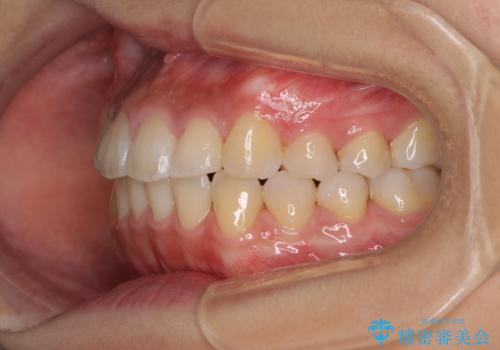

- 前歯のでこぼこと乳歯が残るほどの八重歯を気にして来院された患者様です。

非抜歯にてワイヤー矯正にて治療することとしました。(ただし、親知らずと乳歯は抜歯)

犬歯は歯根が太く長いため、移動には時間を要します。しかし、犬歯は機能面から考えて残すことを選択したいため、長期間をかけて治療を行うこととしました。

治療の度に歯列が改善していったため、長期間の治療も楽しく過ごしていいただき、満足のいく仕上がりとなりました。